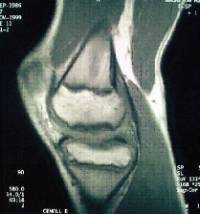

Es una patología ocasionada por una isquemia transitoria del hueso subcondral pudiendo progresar hasta llegar a provocar el desprendimiento del mismo.

Se localiza con mayor frecuencia en el cóndilo femoral interno y su pronóstico varía en función de la edad de presentación (poco frecuente por debajo de los 10 años) y la estabilidad de la lesión.

El tratamiento pasa por limitar actividad deportiva de impacto , variar el eje de carga mecánico de la extremidad y puede ser necesaria la intervención quirúrgica.